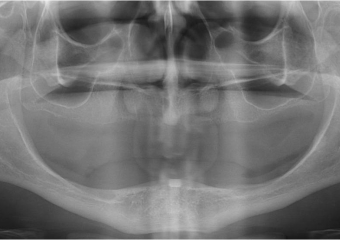

Raio x final